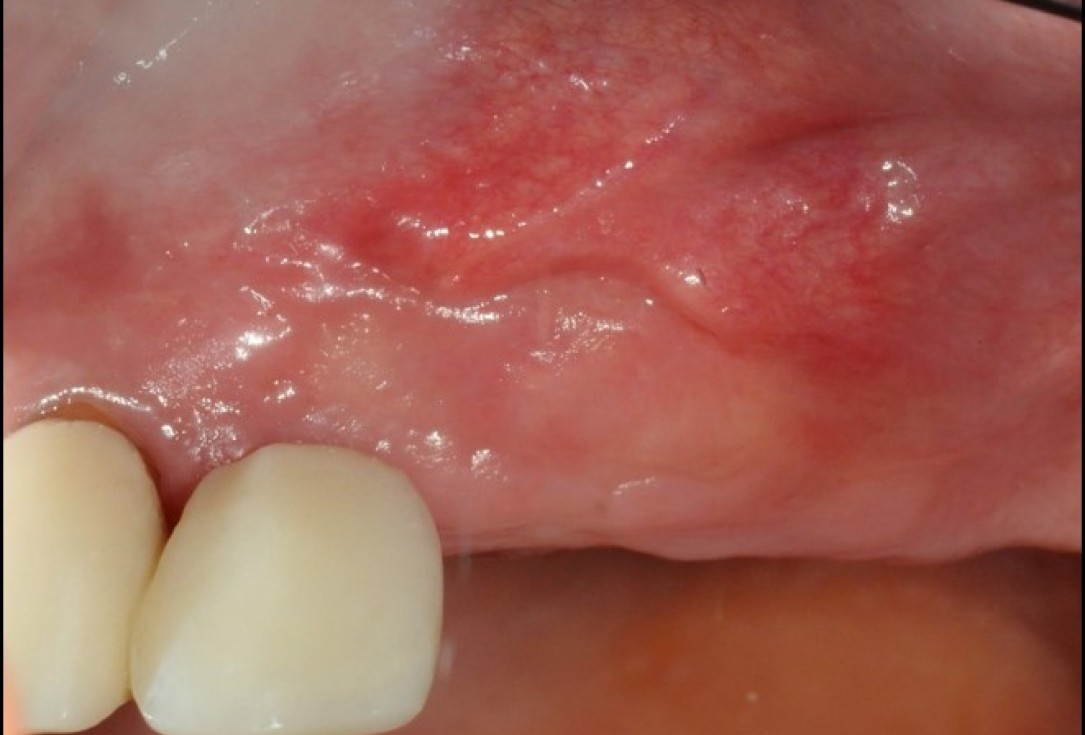

Lack of sufficient keratinized mucosa following extensive horizontal ridge augmentation